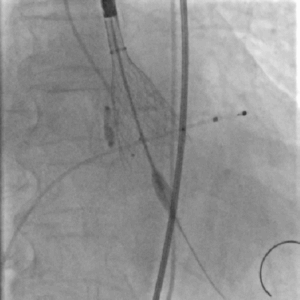

球囊扩张

瓣膜定位

快速释放瓣膜

瓣膜到位,患者突然心跳骤停,立即给予胸外心脏按压并快速释放瓣膜,之后继续胸外心脏按压,肾上腺素静推。

瓣膜完全释放,形态良好、无周漏

经过以上处理,患者心跳恢复、血压回升、术后压力阶差降至小于3-5mmHg,瓣膜形态良好,极少量瓣周漏,但患者随后出现持续性室性心动过速。